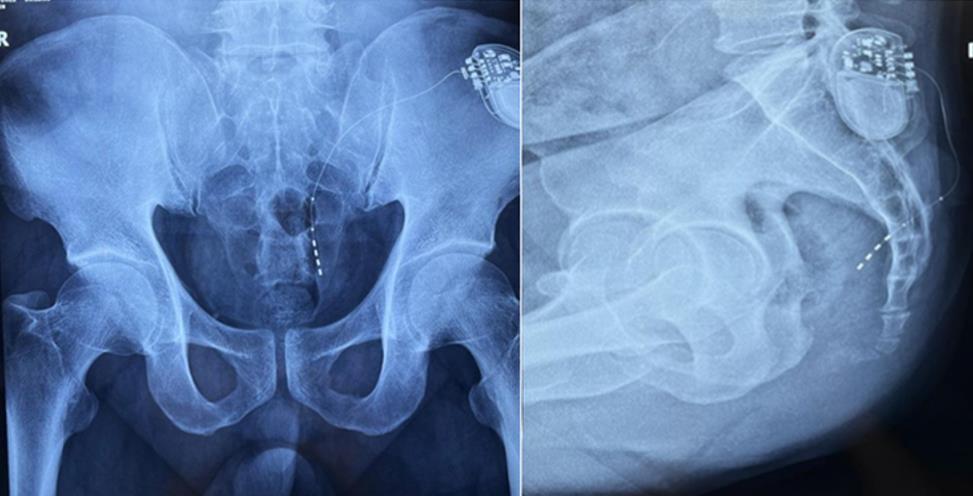

该患者两年前被诊断患有膀胱过度活动症(OAB),出现严重尿频、尿急、尿细线等症状,医生为其做了骶神经调控手术。近期,患者症状又开始加重,生活质量受到影响,为减轻症状,改善生活,患者前往南医大二附院就诊。卫中庆主任及其团队在查看患者病情后,决定重新调整电极刺激位置,将刺激点由原左侧骶4神经孔改为骶3神经孔,通过新的神经调节顺利地改善了症状。

患者术前影像